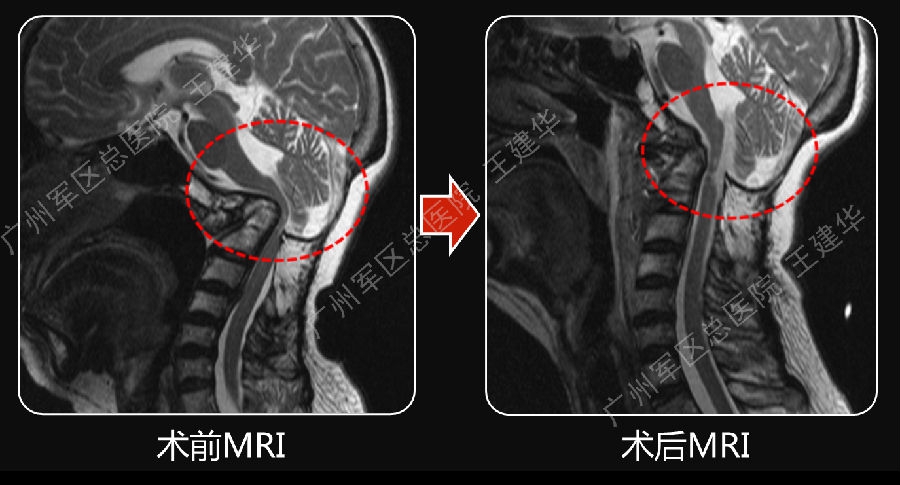

手术前后对比

手术后CT显示,陷入枕骨大孔的齿突获得下拉复位

术后MRI发现,患者的颅底凹陷,脊髓空洞和Chiari畸形均获改善